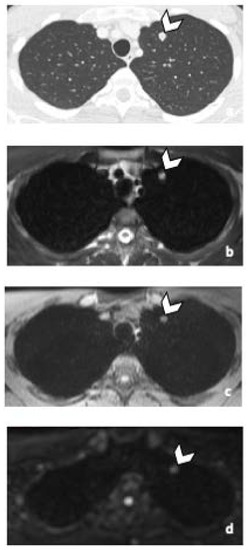

Figure 1.

29-year-old man with NSGCC. Axial T2-weighted MR image (a), coronal reformatted 3D T1 GRE Fat-Sat (c) and high b-value DWI (inverted greyscale, b = 1000 s/mm2) (d) of MR images of the whole body and axial CT image after intravenous injection of iodinated contrast agent (Xenetix 350®) and per os contrast opacification (Telebrix Gastro® 5%) (b), showing interaorticocaval enlarged pathological lymph nodes (arrowheads), identified by both readers during MRI and CT readings. The lymphadenopathies show an intermediate to high signal intensity on T2 (a), an heterogenous low and high signal intensity on T1 (c) compatible with histological component of NSGCC and a restricted Diffusion (d). Note the presence of a left supraclavicular lymphadenopathy visible on DWI (d: arrow). Abbreviations: NSGCC: Non-Seminomatous Germ Cell Cancer, 3D: Three Dimensional, T1 GRE: T1 Gradient Echo, DWI: Diffusion Weighted Imaging, MRI: Magnetic Resonance Imaging, CT: Computed Tomography.